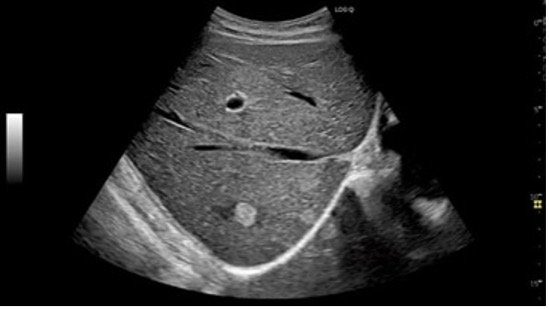

写真:肝臓 血管腫